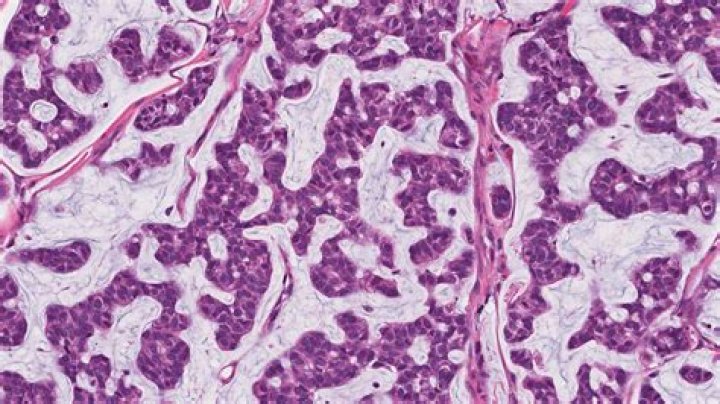

Mucins are high-molecular weight glycoproteins typically found in normal skin in small amounts. There are several reports regarding different types of cutaneous mucinosis. In this report, we discuss mucins in dermatopathology as a diagnostic clue of some well-known entities and some less frequent cutaneous diseases.

All involve accumulation in the skin of abnormal amounts of mucin. This is a jelly-like complex carbohydrate substance, called hyaluronic acid, that occurs normally as part of the connective tissue in the dermis or mid-layer of the skin. The abnormal deposits that occur in mucinoses can be localised or widespread.

In most protocols, sections are stained with the standard Alcian blue (pH 2.5) method followed by the PAS technique. The Alcian blue at a pH of 2.5 will stain all acid mucins deep blue but will not color the neutral mucins. The subsequent application of the PAS technique will stain the neutral mucins bright magenta.